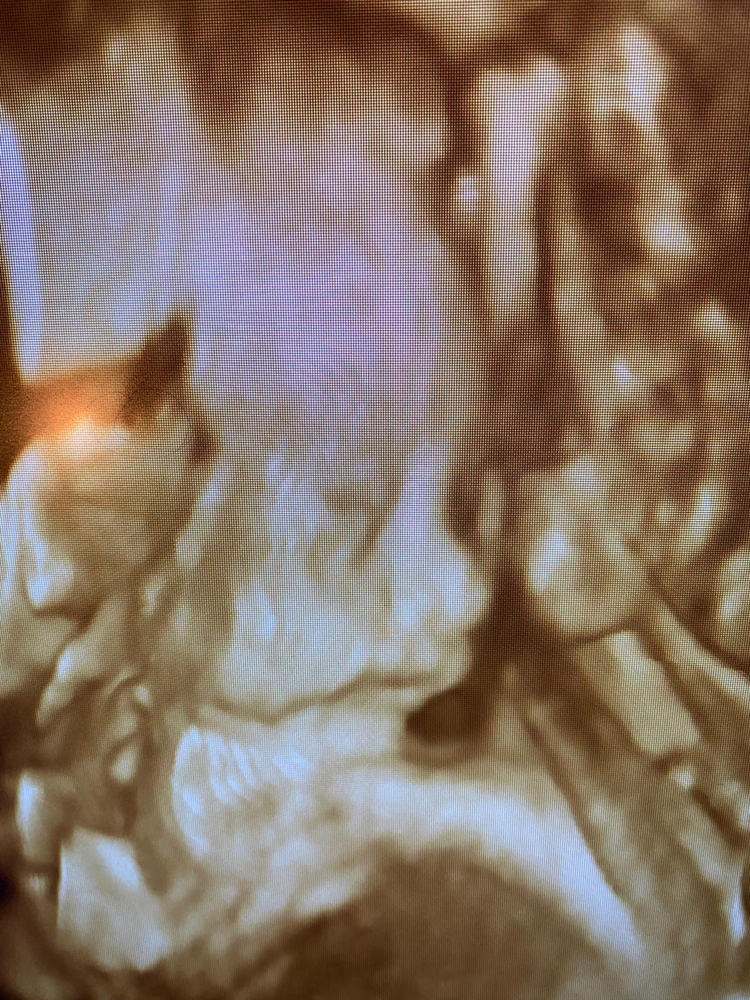

Later, when Jashley was 24 weeks along, she returned to the clinic for a 3D/4D ultrasound, which revealed a baby girl. Jashley’s child is due in April, Avila said.